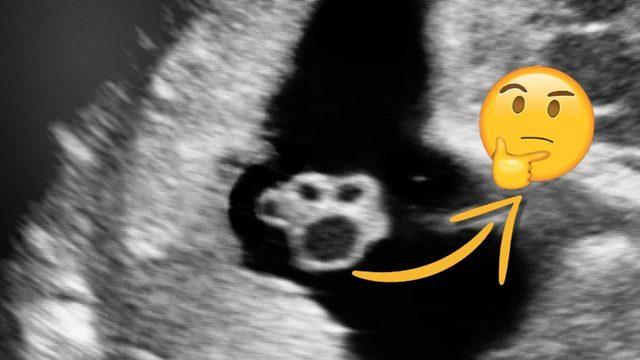

Özellikle hamilelik döneminde tüketilen alkolün bebeklerdeki olumsuz etkilerini araştıran Hollandalı araştırmacılar, az miktarda alkolün bile bebeklerin fiziksel yapısında ve bilişsel yapısında ciddi değişimlere neden olduğunu gözlemledi.

İlkokul çağındaki 5.600 çocuk üzerinde yapılan araştırmada makine öğrenimi ve yapay zeka desteğiyle çocukların 200 fizyolojik farklılığı incelendi. Yapılan araştırmada anneleri hamilelik dönemindeyken haftada 1 kadeh şarap (ya da eş değer oranda diğer alkollü içecekler) tüketen çocuklarda daha kısa burun, göz altında şişlikler, koku almada kayıp, göz kapaklarında tembellik ve daha pek çok fizyolojik farklılığa rastlandı. Alkol tüketimi arttıkça fizyolojik farklılıklara ek olarak psikolojik ve bilişsel sorunların da ortaya çıktığı ve çocuklarda iletişim kurma, anlama ve düşünme yeteneklerinde az da olsa azalma yaşandığı belirtildi.